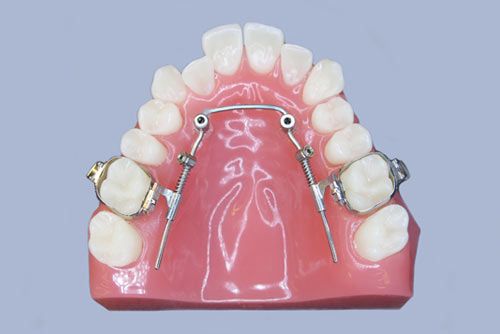

Insertion von Bone-Ankern, Minischrauben und Gaumenimplantaten

Kieferorthopädische Schrauben

Kieferorthopädische Schrauben sind sogenannte Knochenverankerungssysteme und dienen der maximalen Verankerung bei aufwändigen Zahnbewegungen.